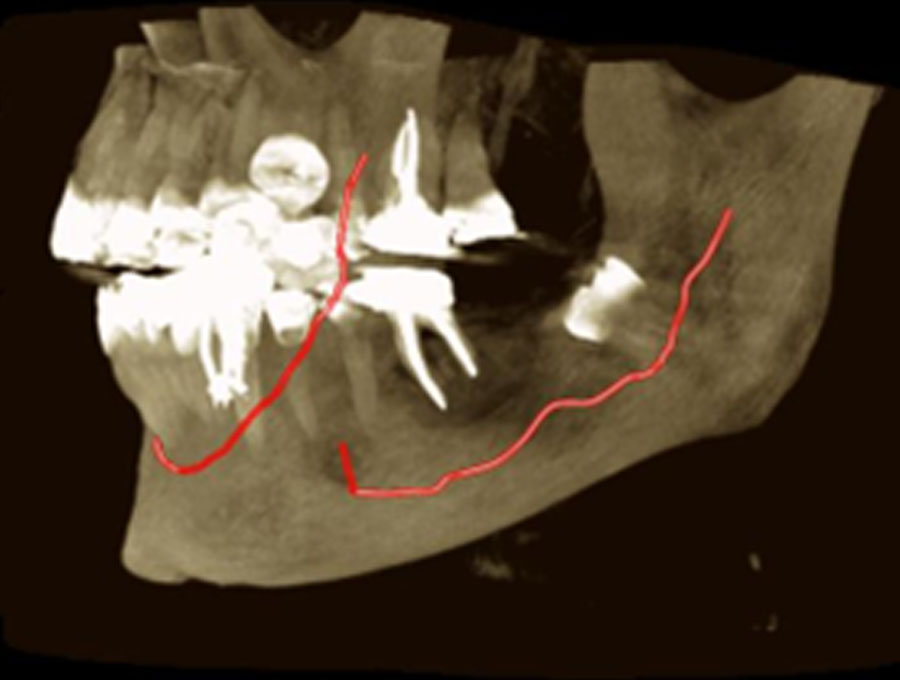

Ατελής ενδοδοντική θεραπεία που οδήγησε σε περιακρορριζική καταστροφή.

Η επανάληψη της ενδοδοντικής θεραπείας δεν οδήγησε σε πλήρη επούλωση της βλάβης,

καθώς είναι αναγκαία και η περιοδοντική θεραπεία του δοντιού.